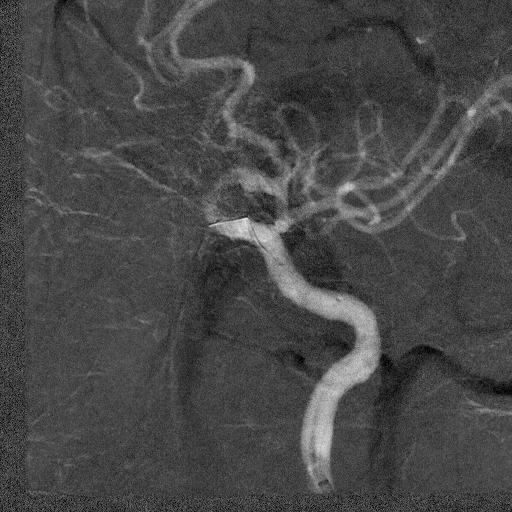

左侧颈总动脉正侧位造影

支架释放后造影显示残余狭窄40%。

术后造影显示支架内无明显残余狭窄,颅内血管无明显栓塞。